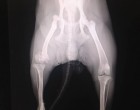

A rtg lapján: jobb oldali csípőcsont ficam és I tipusú Harris törés a distalis epiphyzisben, jobb oldali könyökízület ficam. A tüdőben enyhe beszűrődés látható, hasüregben folyadék nem látható, hólyag látszódik.Szív, tüdő rendben. A gyomra tele volt, a balesete előtt ehetett. A szája "csak" azért vérzett, mert a sokk következtében megharapta a száját, vagy a nyelvét.